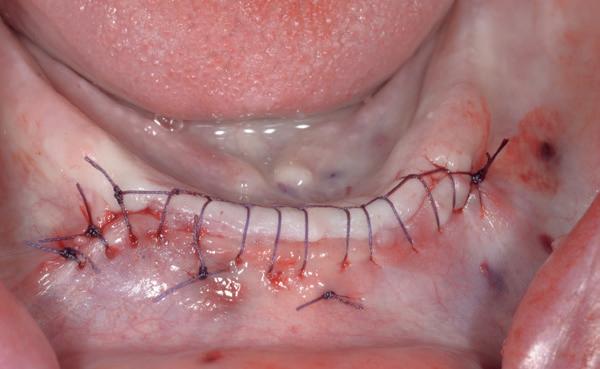

Voor de behandeling kreeg de patiënt Amoxicilline 500mg 3dd1 gedurende een week voorgeschreven waarbij er een dag voor de chirurgie gestart werd, als pijnstilling Ibuprofen 600 mg 3dd1 voor een week en Blue M Mouthwash voor de mondspoeling gedurende de eerste 2 weken. Na de anesthesie werd een incisie gemaakt van tuber tot tuber en werd de

3. Na flap een guide pin in foramen incisivum

4. Plaatsen van 6 implantaten en kaakverbreding 14

5. Primaire sluiting met een door-

mucosa zowel buccaal als palatinaal afgeschoven. Het is belangrijk om te realiseren dat de bovenkaak zachter alveolair bot heeft dan de onderkaak en dat stug periost op de kaak kan zitten. Daarom is het van belang om te starten met curettage van de kaak. Na het vrijleggen van de canalis incisivum, werd een guide pin in de canalis geplaatst. Het kanaal loopt loodrecht op de kaak en kan dienen als referentie

lopende hechting

voor de implantaten (afbeelding 3). Hierna werd met een meetinstrument de locaties van de implantaten uitgemeten en werd een initiële osteotomie op deze locaties gemaakt. Voor de 16 werd een crestale sinusbodemelevatie met Densah boren uitgevoerd. Hierbij werd het zachte bot gecondenseerd om naar crestaal geduwd te worden, waarna het membraan van Schneider meelifte. Door de osteotomie werden 1cc botkorrels geplaatst en daarna direct het implantaat. Ter plaatse van de 14 zat een verticaal botdefect, na plaatsen van dit implantaat, werd de kaak verticaal verhoogd. Er werden 6 implantaten van het merk AnyRidge (MegaGen Implant Company, Korea) geplaatst met diameter 5.0 mm aan de distale zijdes, diameter 4.5 mm bij de premolaren en 4.0 mm implantaten bij de laterale incisieven (afbeelding 4).

Ter plaatste van de 16 en 14 werden verticale matrashechtingen geplaatst, waarna er één doorlopende hechtingen van tuber tot tuber volgde met een 4-0 gevlochten hechtdraad (afbeelding 5). Gedurende de eerste 2 weken van de genezing is het van essentieel belang voor de wondgenezing, dat de patient geen bovenprothese draagt. Deze werd daarom ingenomen, met de uitleg dat direct dragen van de bovenprothese een nadelige invloed heeft op de genezing van de kaak, de botopbouw en de implantaten. Patiënt kwam 2 weken na de chirurgie retour voor het verwijderen van de hechtingen, waarna de binnenzijde van de bovenprothese werd uitgeslepen en voorzien werd van een softliner als nieuwe tijdelijke voering voor retentie van de bovenprothese. Vanwege de kaakverhoging en sinusbodemelevatie, werd 6 maanden genezing afgewacht van het bot en integratie van de implantaten.